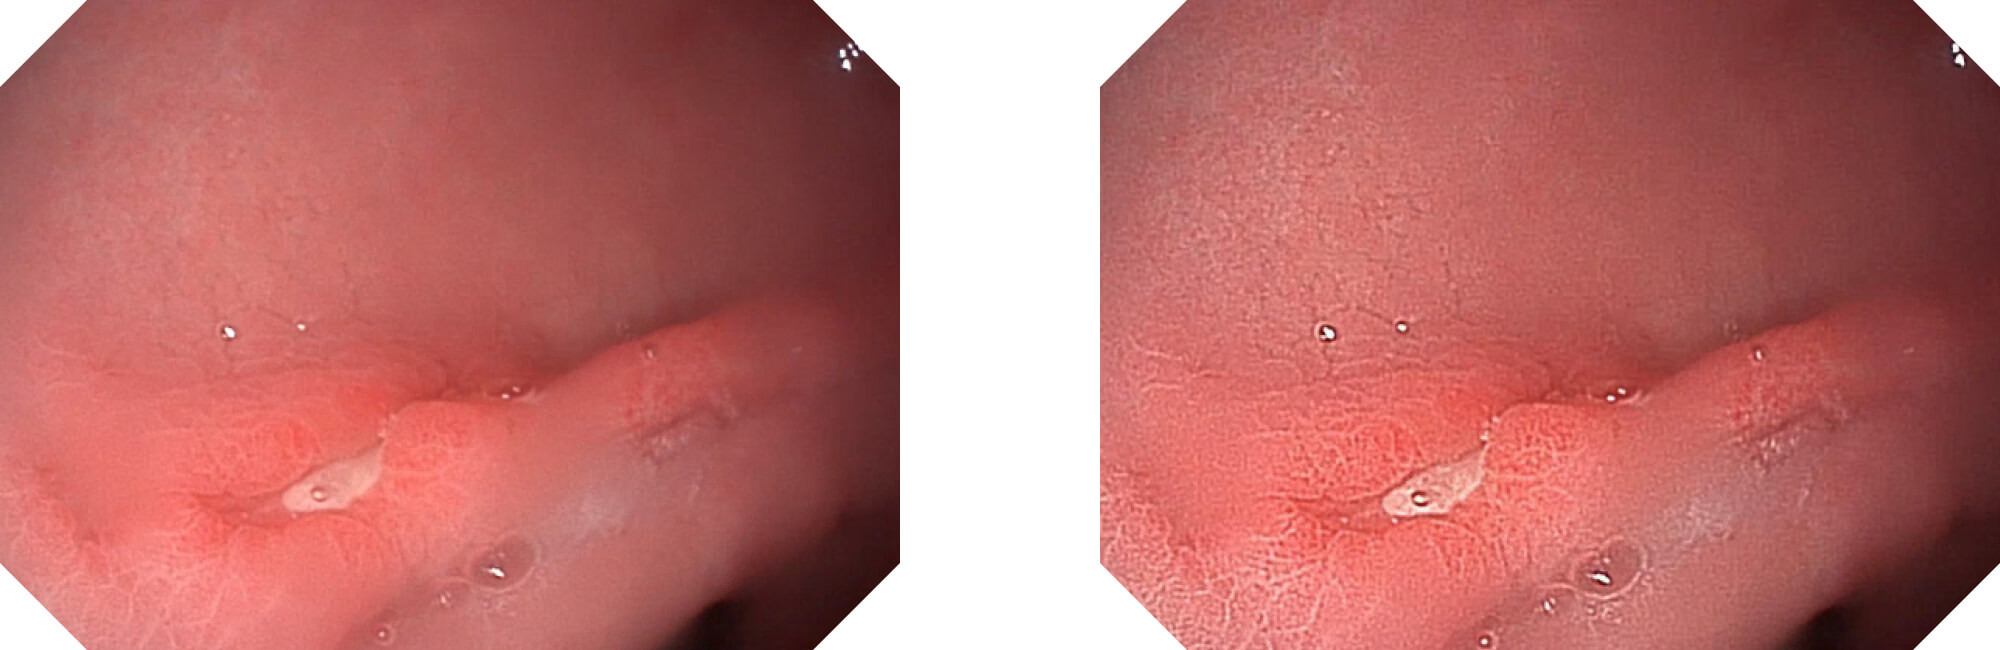

高清数字信号结合构造强调和色彩增强,多重图像处理技术能让每一个图像都清晰可见。

构造强调

色彩增强

电子放大